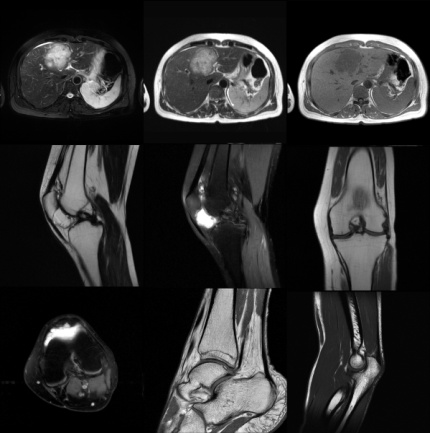

奥泰医疗1.5T MRI 图像质量反馈

腰椎和髋关节图像

腹部骨关节图像